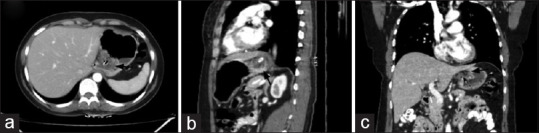

导读:在过去的十年中,随着腹腔镜抗反流手术(LARS)的数量和可接受性在长期医学治疗中不断增加,因此,盆底包裹术的并发症间歇性地出现胃灼热和吞咽困难的复发症状。内窥镜检查和钡餐是初步调查进行怀疑眼底包裹失败。然而,随着多层计算机断层扫描(CT)和多平面重建的容易获得以及对钡检查的熟悉程度的降低,外科医生熟悉包膜失败的各种表现将是谨慎的。目前,还没有公认的标准来报告应用程序封装失败。我们对使用CT扫描治疗基底膜包裹失败的文献进行了全面的回顾,并与著名的放射科医生和外科医生组成了一个多学科的疝气小组,讨论了CT扫描在治疗可疑包裹失败中的作用。在完成了对大约43例包膜失败患者的初步研究后,我们创建了一个标准的CT报告格式,这有助于我们管理即使是最复杂的病例。这个标准的报告格式可以被全世界的受训者和外科医生使用。这将导致报告的一致性,将有助于决策,也将有助于创建国家和国际主要包装失败和重做基金申请注册。患者与方法:对43例多层螺旋CT膜片失效患者进行评价,分析膜片失效类型及膜片完整性维持的影响因素。采用一种新颖的结构化报告清单来描述术后影像学发现。结果:描述了患者的人口学特征、术后影像学和术中表现。不同类型的包装失败-阻碍类型和相关病理分析相对频率在包装失败。新颖的结构化报告包括LARS术后患者的包裹完整性和失败并发症。结论:眼底包裹失败是LARS术后常见的并发症。一种新的结构报告与检查表将帮助外科医生评估术后复发症状的患者。多层螺旋CT是初步内镜评估后疑似包裹失败的理想成像方式。冠状面和矢状面重建的多平面成像有助于了解包裹层的完整性及其检测故障/迁移的能力。

Introduction: With increasing numbers and acceptability of laparoscopic anti-reflux surgery (LARS) procedures over long-term medical treatment in the past decade, it follows that the complications of fundoplication wrap are seen intermittently with recurrent symptoms of heartburn and dysphagia. Endoscopy and barium swallow are the initial investigations performed for suspected fundoplication wrap failures. However, with easy availability of multislice computed tomography (CT) and the multiplanar reconstructions along with reduction in familiarity with barium examinations, it would be prudent for the surgeons to familiarise themselves with various appearances of wrap failure. Currently, there is no accepted standard to report a fundoplication wrap failure. We did a thorough literature review on the use of CT scans for fundoplication wrap failure, created a multidisciplinary hernia team with prominent radiologists and surgeons and discussed the role of CT scans in the management of suspected wrap failure. After completing a pilot study with around 43 patients of wrap failure, we created a standard CT reporting format which helped us in the management of even the most complex cases. This standard reporting format can be used by trainees and surgeons worldwide. This would lead to uniformity in reporting, would help in decision-making and would also help create national and international primary wrap failure and redo fundoplication registry.

Patients and methods: A total of 43 patients of wrap failure of multislice CT evaluation were analysed for type of failure along with factors responsible for the maintenance of integrity of the wrap. A novel checklist with structured reporting was used for the description of the post-operative imaging findings.

Results: The demographic characteristics, post-operative imaging and intraoperative findings were described. The different types of wrap failure - Hinder types and associated pathologies were analysed for relative frequency in wrap failures. The novel structured reporting included wrap integrity and failure complications in post-operative patients of LARS.

Conclusion: Fundoplication wrap failure is not an uncommon complication seen after LARS. A novel structured report with checklist will help the surgeons to evaluate the post-operative patient with recurrent symptoms. Multislice CT is the ideal modality for imaging suspected wrap failures after primary endoscopic evaluation. Multiplanar imaging with coronal and sagittal reconstructions is useful for understanding the integrity of the wrap and its ability to detect failure/migration.